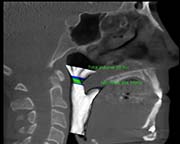

6 months post surgery

Surgical Plan